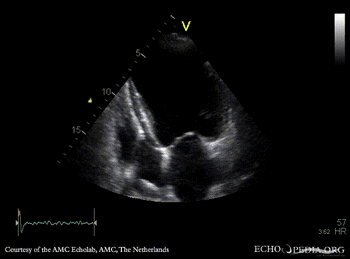

| Courtesy of: AMC Echolab, AMC, The Netherlands | |

| A4CH: apical aneurysm of left ventricle | A2CH: apical aneyrysm of left ventricle |

| A3CH | |